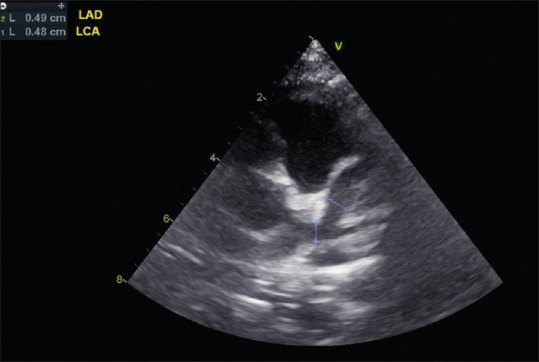

川崎病(Kawasaki disease, KD)是一种病因不明的儿童多器官和系统的全身性炎症性疾病。基本的病理改变是中小动脉,主要是冠状动脉的全血管炎。它现在是发达国家儿童获得性心脏病的主要原因,并导致心绞痛、心肌缺血/梗死的早期发展,甚至是成年早期的心源性猝死。虽然对KD没有明确的诊断测试,但准确的诊断取决于临床表现是否符合诊断标准。超声心动图是一种众所周知的无创工具,用于检测结构异常和评估心血管功能。据报道,它可以准确地检测早期和晚期心血管异常,包括血管周围亮度,缺乏锥形,扩张和冠状动脉动脉瘤形成以及二尖瓣/主动脉反流,心包积液和KD的心肌功能改变。对于KD形态不全及临床表现不符合诊断标准的患者,冠状动脉超声心动图异常可为KD的早期诊断提供帮助。长期定期超声心动图随访是KD患者首发冠状动脉异常的基础和必要研究。本文回顾并讨论了99篇研究KD超声心动图表现的文章。

Kawasaki disease (KD) is an etiology-unknown but with a generalized inflammatory disorder of multiple organs and systems in childhood. The basic pathologic changes are panvasculitis of the small and medium-sized arteries, mainly the coronary arteries. It is now the leading cause of acquired heart disease during childhood in developed countries and has led to the early development of angina pectoris, myocardial ischemia/infarction, and even sudden cardiac death in early adulthood. Although there is no definitive diagnostic test for KD, the accurate diagnosis is dependent on the clinical presentations to meet the diagnostic criteria. Echocardiography is a well-known noninvasive tool to detect structural abnormalities and evaluation of cardiovascular function. It has been reported to detect accurately the early and late cardiovascular abnormalities, including perivascular brightness, lack of tapering, dilatation, and aneurysmal formation of coronary arteries as well as the mitral/aortic regurgitation, pericardial effusion, and myocardial functional changes in KD. In cases of incomplete form of KD and patients whose clinical manifestations did not meet the diagnostic criteria, abnormal echocardiographic findings of coronary artery may provide the assistance for early diagnosis of KD. Long-term periodic echocardiographic follow-up is the basic and essential study for patients of KD with initial coronary arterial abnormalities. Ninety nine articles that studied echocardiographic findings of KD had been reviewed and will be discussed.